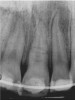

Figure 1b  Panoramic (A) and periapical radiographs (B, C) reveal the absence of periapical rarefaction in the area of the upper right central incisor. However, evidence of apical periodontitis can be seen clearly using the CBCT21 (D, E).

Figure 1b

Figure 1c  Panoramic (A) and periapical radiographs (B, C) reveal the absence of periapical rarefaction in the area of the upper right central incisor. However, evidence of apical periodontitis can be seen clearly using the CBCT21 (D, E).

Figure 1c

In addition to linear accuracy, it has been suggested that CBCT can have diagnostic accuracy with regards to periapical lesions.17-19 In one of these studies,17 periapical lesions were analyzed with CBCT, then surgically excised and biopsied to compare with histology. The authors found comparable results. Although the study showed promising results with CBCT, the researchers conceded that histology remains the gold standard in the diagnostic armamentarium. In another study,19 the ability to identify periapical lesions was assessed using radiographs and spiral CT. With CT, 100% of lesions were identified, while only 78% were identified with radiographs alone. Concomitantly, the location of the lesions proximal to the inferior alveolar nerve was visualized more readily with CT (100% vs 39%). Figure 1A through Figure 1E illustrate a case in which an endodontically treated tooth appeared normal on panoramic and periapical radiographs. Only CBCT showed the presence of apical pathology.6